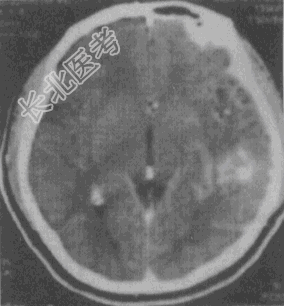

- 单项选择题男性,39岁, "癫痫"发作2次,无发热、肢体活动不适等症状, 根据其CT平扫及强化图像(见图),应首先考虑以下何种诊断

A、星形细胞瘤

B、AVM

C、脑出血

D、脑膜瘤

E、脑梗死